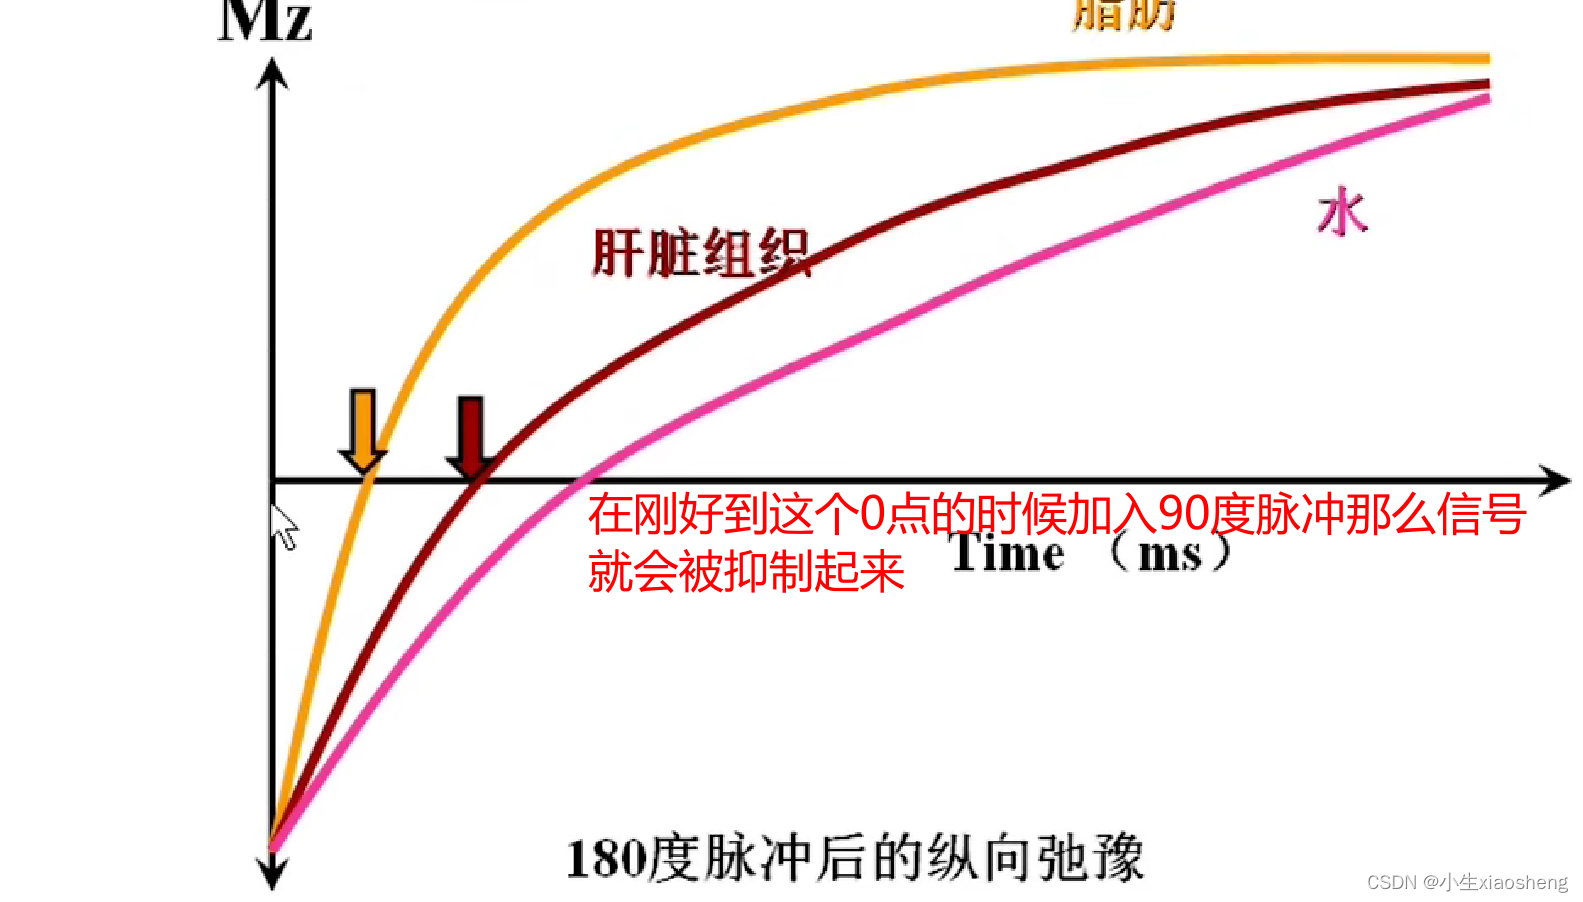

说明时间越长对应的差距也就越大,说明其结果对比好,更容易看出图片。其中TI为反转时间

通过抑制那么在检查的时候就能针对性检查某种组织信号。几种应用我也不想看了😵